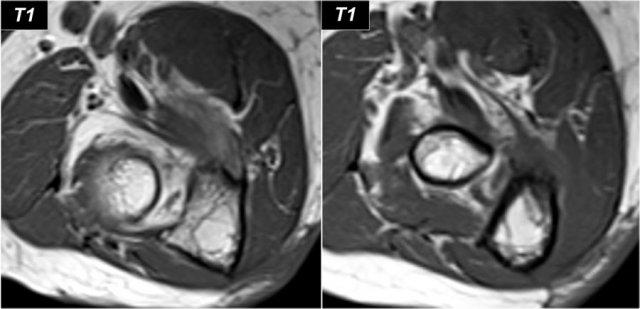

Arthrosis in valgus overload syndrome

Do quá tải valgus, có các lực cắt tác động lên phần sau-trong của khớp cánh tay-trụ.

Lưu ý tình trạng xơ cứng dưới sụn được thấy trên ảnh T1W (mũi tên đỏ).

Trên hình ảnh T2W có phù tủy xương dưới sụn và mất sụn khớp (mũi tên vàng).

Đây là hình ảnh của một vận động viên bóng chày 20 tuổi.

Hãy cuộn qua các hình ảnh.

Trên các hình ảnh mặt phẳng coronal, bó trước của dây chằng UCL hiện rõ đẹp, nhưng lưu ý rằng có sự hình thành gai xương ở phần trong của khớp (mũi tên đỏ).

Khi chúng ta đi xa hơn về phía sau có một vùng nhỏ có tín hiệu thấp (mũi tên vàng), đây là một chỗ bong gân của một phần dây chằng bên trụ (UCL).

Điều này được thể hiện rõ hơn trên phim X-quang.

Continue with the axial scan.

Khi quan sát trên lát cắt ngang (axial), chúng ta có thể nhận thấy sự hình thành gai xương khổng lồ.

Lưu ý rằng dây thần kinh trụ (mũi tên màu xanh) nằm cạnh các gai xương này và những bệnh nhân này có thể biểu hiện bệnh lý thần kinh trụ.